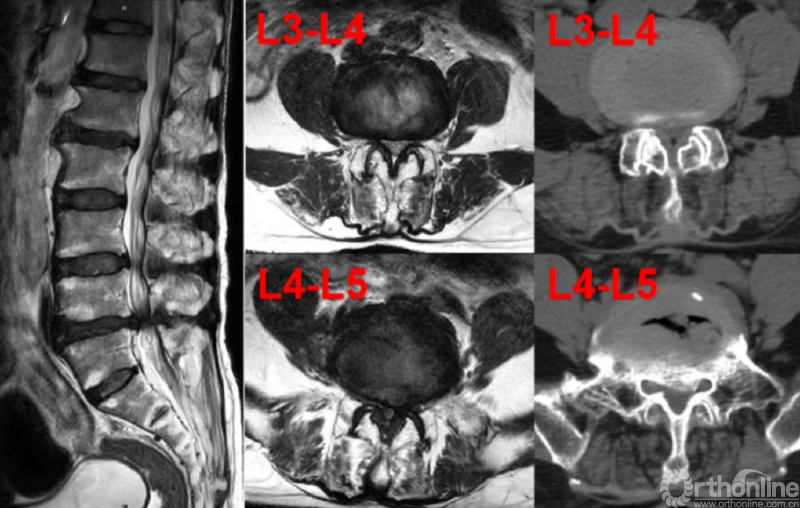

图1.患者术前影像学(MRI+CT)检查结果

考虑到患者腰椎管狭窄症的责任节段为L3-4、L4-5双节段,如按照以往常规单术者分节段操作,手术时间较长,为节约手术时间、降低全麻术中麻醉意外发生率、缩短术后麻醉苏醒时间,费琦主任医师、孟海副主任医师充分讨论及术前准备后考虑尝试双术者同时行L3-4、L4-5双节段UBE-ULBD手术。为了避免出现两位术者操作相互干扰,费琦主任医师于患者左侧行L4-5节段ULBD,孟海副主任医师于患者右侧行L3-4节段ULBD(图2),双术者同时使用两套内镜成像系统和手术器械成功地完成了双节段ULBD手术。整个手术在全麻下进行,手术顺利,手术时间2个多小时,术中出血约100ml,患者术后麻醉苏醒良好,术后即刻感到腰部放松感,第二天佩戴腰围下地行走后自觉下肢疼痛症状明显缓解,结合围手术期ERAS(术后快速康复)的各项管理措施,患者取得了满意的临床疗效。术后复查腰椎CT显示L3-4、L4-5双侧减压充分(图3)。